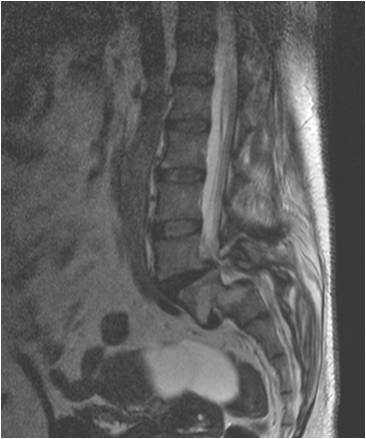

Bel kayması, yani bizi taşıyan omurga kemik sisteminin birbiri üzerinde kayıp omuriliği sıkıştırması, oldukça sık görülen bir rahatsızlıktır. Yürürken sık sık durma isteği bacaklarda uyuşma, yanma hissi ortaya çıkan bu rahatsızlık tedavi edilmezse idrar tutamama, erkeklerde cinsel yetersizlik, yürüyememe, belden aşağısını hissetmeme gibi sonuçlara da yol açabilir. Bel kaymasının tek tedavisi beli titanyum vidalarla sabit hale getirip kaymasını önlemektir. Halk arasında “platin” ya da “vida” ameliyatı olarak adlandırılan bu tedavi yöntemi halk arasında oldukça riskli olarak bilinmektedir. Bu nedenle, bu ameliyatı olması gerekenler bu tedaviden kaçmakta ömür boyu kalitesiz bir yaşam sürmektedirler. Oysa tecrübeli bir cerrahın ellerinde bu ameliyatlar sıfır riskle tamamlanmaktadır. Yeni teknolojilerle tüm bu endişeler ortadan kalkmakta, bilgisayar desteği ile vidalar tam yerine konabilmektedir. Bu sistem sayesinde bel kayması ameliyatları sorunsuz olarak uygulanabilmektedir. Önemli olan doğru zamanda doğru teşhisi koymaktır.

Bel kayması ameliyatları yaklaşık 2-2,5 saat sürmekte, hasta ameliyattan yirmi dört saat sonra ayağa kalkıp kişisel ihtiyaçlarını yardım olmaksızın yapabilir durumda olur. Hastanede iki gün yatması yeterlidir. Bel omurgasına kaymayı önlemek amacıyla titanyum vidalar konmaktadır. Bu vidalar ömür boyu hastada kalmaktadır. Ameliyatta cilt dikişi konmamaktadır. Gelişen yeni teknolojilerle, tecrübeli bir cerrahın elinde felç olma sakat kalma riski yoktur.